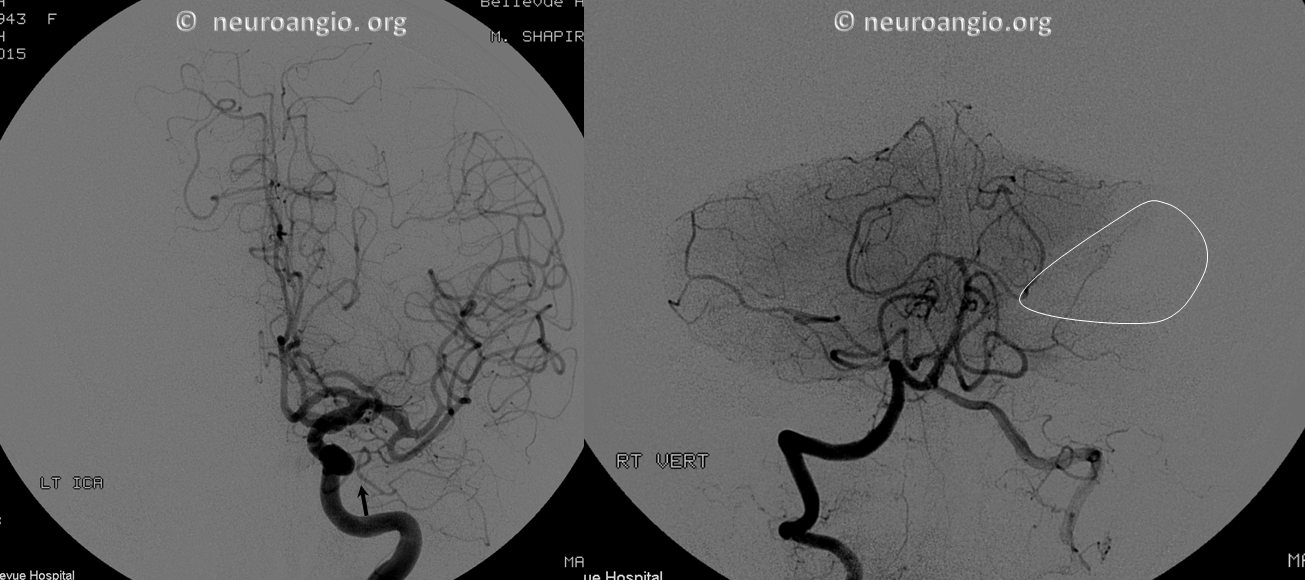

Want more? How about this — see below — the left AICA is hypoplastic. Left PICA (white arrows) supply is limited to vermis. The left SCA is small. How come? There are two possibilities — either the tissue is missing (infarcted, resected, etc), or there is yet another source of supply. The answer is Trigeminal Artery — (black arrows). It again often supplies “AICA territory”. However, insofar as there is really no such thing as “AICA territory” — it being in balance as we keep saying with SCA and PICA — the extent of trigeminal cerebellar supply is as variable as anything else. Here, it is responsible for a big chunk of it (white oval in frontal view), self-evident in lower right lateral view — taking care of both lateral and inferior right hemisphere.

Trigeminal Supply of Superior Cerebellar, AICA, and lateral / hemispheric PICA

Neat. And extremely rare — i am not sure there is another example out there. I am very sure however that there are many people like that walking around, with no problems at all.

I guess that would be Saltzman IIIA+IIIB+IIIC/2. This is either very advanced algebra or a reflection on classifications in general — you decide. The important thing is to put everything together and understand what goes where

Angio shows large trigeminal with clear supply of the SCA on lateral view. Vert injection shows no right SCA. There is a diminuitive branch from mid-basilar projecting laterally — that is likely the right labyrinthine artery — what is embryologically solid AICA territory. The rest is taken by the trigeminal. The right PICA is limited to vermian territory. The inferolateral hemisphere is supplied by the trigeminal as well. Dont look for arrows. You should figure it out.